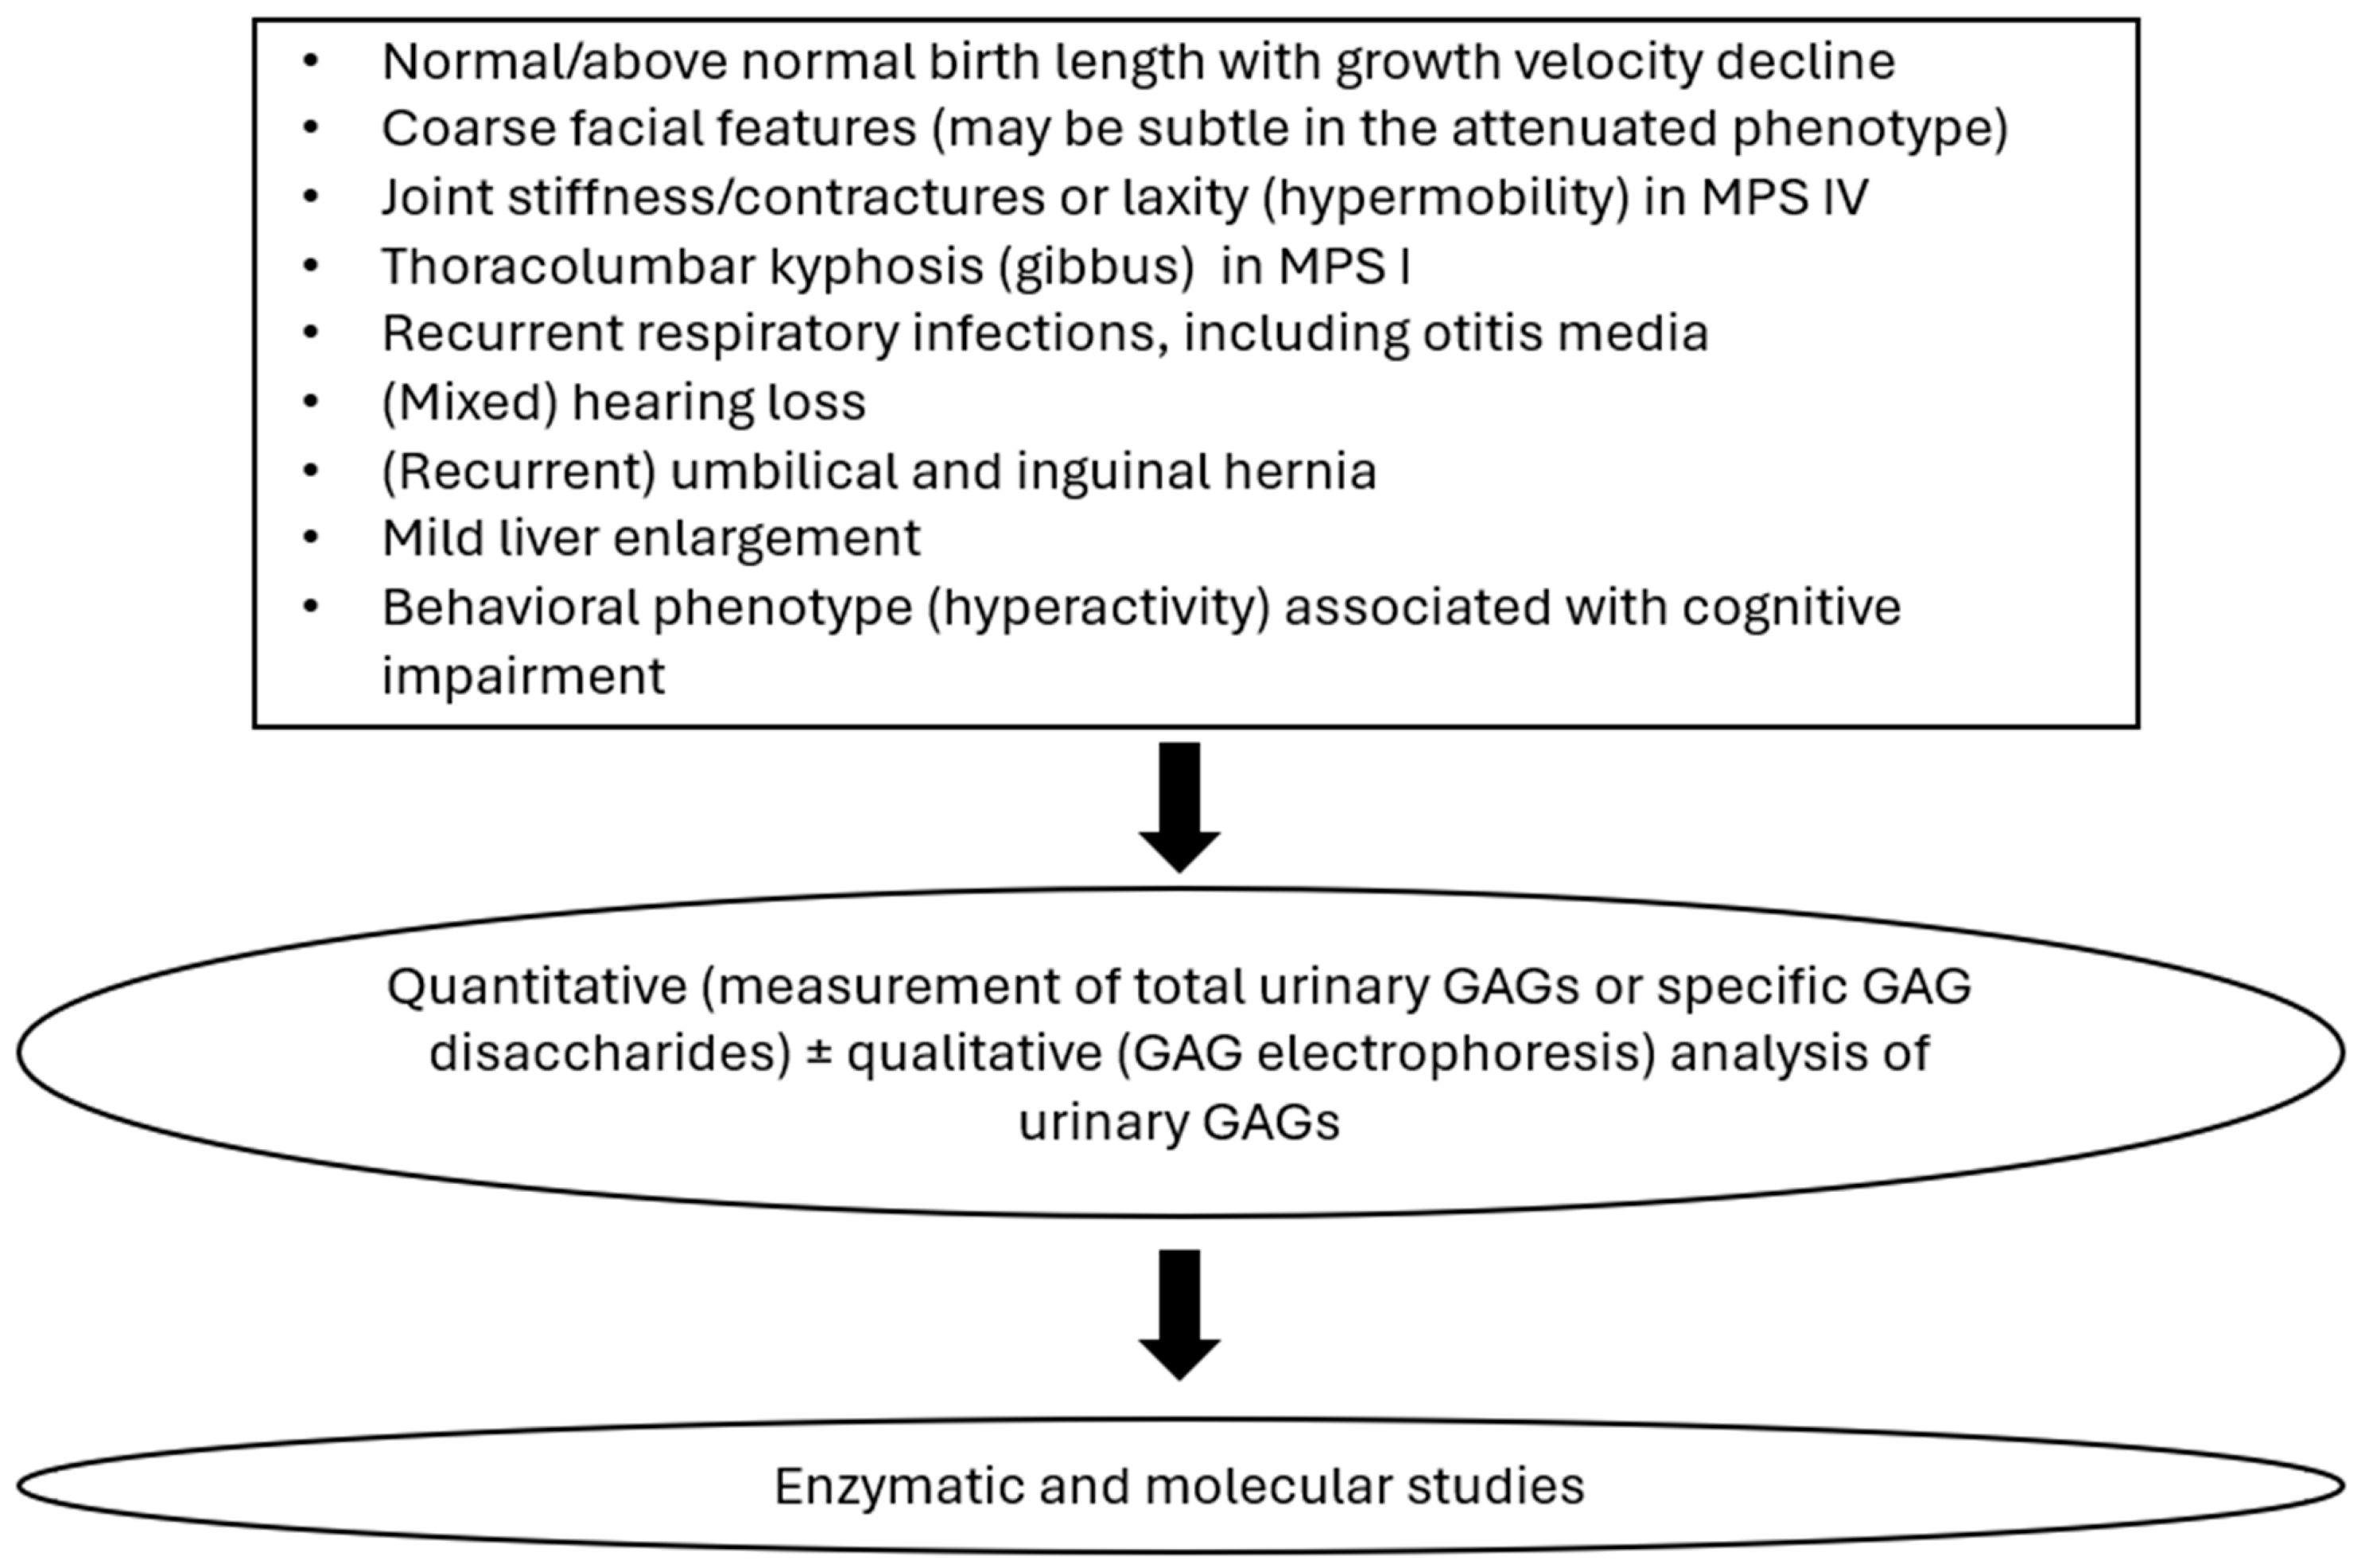

3. Clinical Manifestation of MPSs

3.1. Main Clinical Symptoms Regarding Accumulated GAGs

4. Biochemical Diagnostics